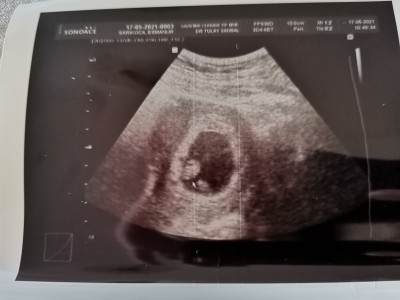

Çok şükür 7 buçuk haftalıkken bugün kalbini duyduk. Allahım böyle bir mutluluk olamaz. Sesini duyduğumdan beri ayağım yere basmıyor. Yanındaki bebeğin eşi mi acaba?

Bu arada yanındaki yolk kesesi halk dilinde evet eşi deniyor maşallah pıtırcıga :)

Yok tek bebek ama eşi falan diyorlar ya o galiba ben de doktorda fark etmedim sonradan bakınca fark ettim

Yolk sac kesesi canım o belli haftaya kadar bebek ondan besleniyor sonra o kayboluyor bebegin kordon bagi oluşuyor bebek ondan beslenmeye başlıyor.  Bebegin eşi dediğimiz şey kesesi

Şuan için yolk kesesi canım. Eş 13-13 ten sonra oluşmaya başlıyor ☺️ sağlıkla gelsin kuzucuk ❤️